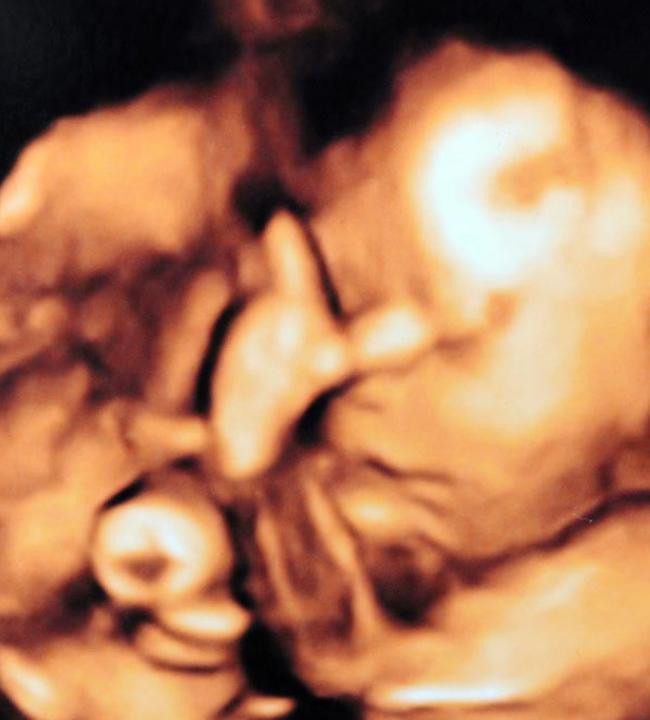

Ce a aratat un bebelus nenascut, in timpul ecografiei. Mama: "Copilul acesta imi va face probleme"

Copiii incep sa faca nazbatii pe la varsta de 2 ani. Nu este si cazul unui bebelus, care si-a surprins parintii inainte ...

FOTO. Surpriza de proportii pentru o tanara care si-a facut o ecografie de sarcina.Ce apare pe ecran

O tanara care va deveni curand mamica si-a facut o ecografie, ca sa vada cum se simte bebelusul. Si ea si sotul ei au ...